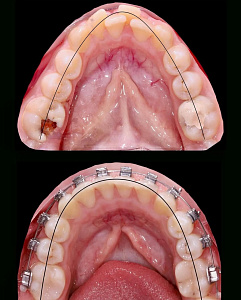

03.11.2025

Тохтиева Дана

Врач-ортодонт

repost be @d4anax end @orthodana.t

История одного ретенированного клыка. Мой первый максимально волнительный опыт с ретенцией. Лечение продлилось 2 года и 4 месяца. Были брекеты, винт, изгибы и другие, пружины, накладки, эластики, в общем - ВСЁ. Результат вышел красивый, на мой взгляд. Сейчас пациент уже готов без брекет-системы, ждем протезирования в области 12/22. По идее, дальше будет HOLLYWOOD SMILE, не иначе. Пациент счастлив, а я еще больше.

История одного ретенированного клыка. Мой первый максимально волнительный опыт с ретенцией. Лечение продлилось 2 года и 4 месяца. Были брекеты, винт, изгибы и другие, пружины, накладки, эластики, в общем - ВСЁ. Результат вышел красивый, на мой взгляд. Сейчас пациент уже готов без брекет-системы, ждем протезирования в области 12/22. По идее, дальше будет HOLLYWOOD SMILE, не иначе. Пациент счастлив, а я еще больше.